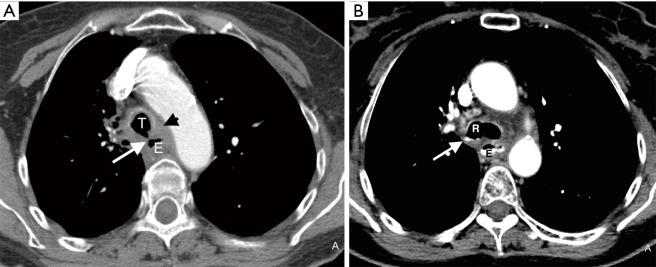

Esophago-airway fistula (EAF) is an abnormal connection between the esophagus and the trachea or a major bronchus. While contrast esophagography remains the primary radiographic tool for the diagnosis of EAF, computed tomography (CT) is often employed in its evaluation. A systematic analysis of CT findings of EAF in adults has not been previously published. The goal of our study is to determine the direct and indirect CT findings of EAF in adults.

Twenty-six patients (median age: 56 years; range, 25-79 years; F=13, 50% and M=13, 50%) with confirmed EAF were identified. Half of the patients had an underlying malignancy. On CT, a direct connection between the esophagus and the airway was identified in most cases (22/26; 85%). Common indirect CT findings of EAF included esophageal wall thickening (21/26, 81%), mediastinal fatty stranding (21/26, 81%), airway wall thickening (20/26, 77%), fluid or debris within the airways (17/26, 65%), and focal or diffuse esophageal dilation with air (17/26, 65%). Mediastinal fluid collections were infrequently seen (4/26, 15%), but findings of aspiration or other pneumonia were common (19/26, 73%).

食管气道瘘(EAF)是食管与气管或主支气管之间的异常连接。虽然食管造影仍是诊断EAF的主要影像学检查方法,但计算机断层扫描(CT)常用于其评估。此前尚未发表过对成人EAF的CT表现的系统分析。我们研究的目的是确定成人EAF的直接和间接CT表现。

共确定了26例确诊为EAF的患者(中位年龄:56岁;范围25 - 79岁;女性13例,占50%;男性13例,占50%)。半数患者有潜在恶性肿瘤。在CT上,大多数病例(22/26;85%)可发现食管与气道之间的直接连接。EAF常见的间接CT表现包括食管壁增厚(21/26,81%)、纵隔脂肪条索影(21/26,81%)、气道壁增厚(20/26,77%)、气道内液体或碎屑(17/26,65%)以及局限性或弥漫性食管扩张并伴有气体(17/26,65%)。纵隔积液较少见(4/26,15%),但吸入性或其他肺炎的表现常见(第十九/26,73%)。